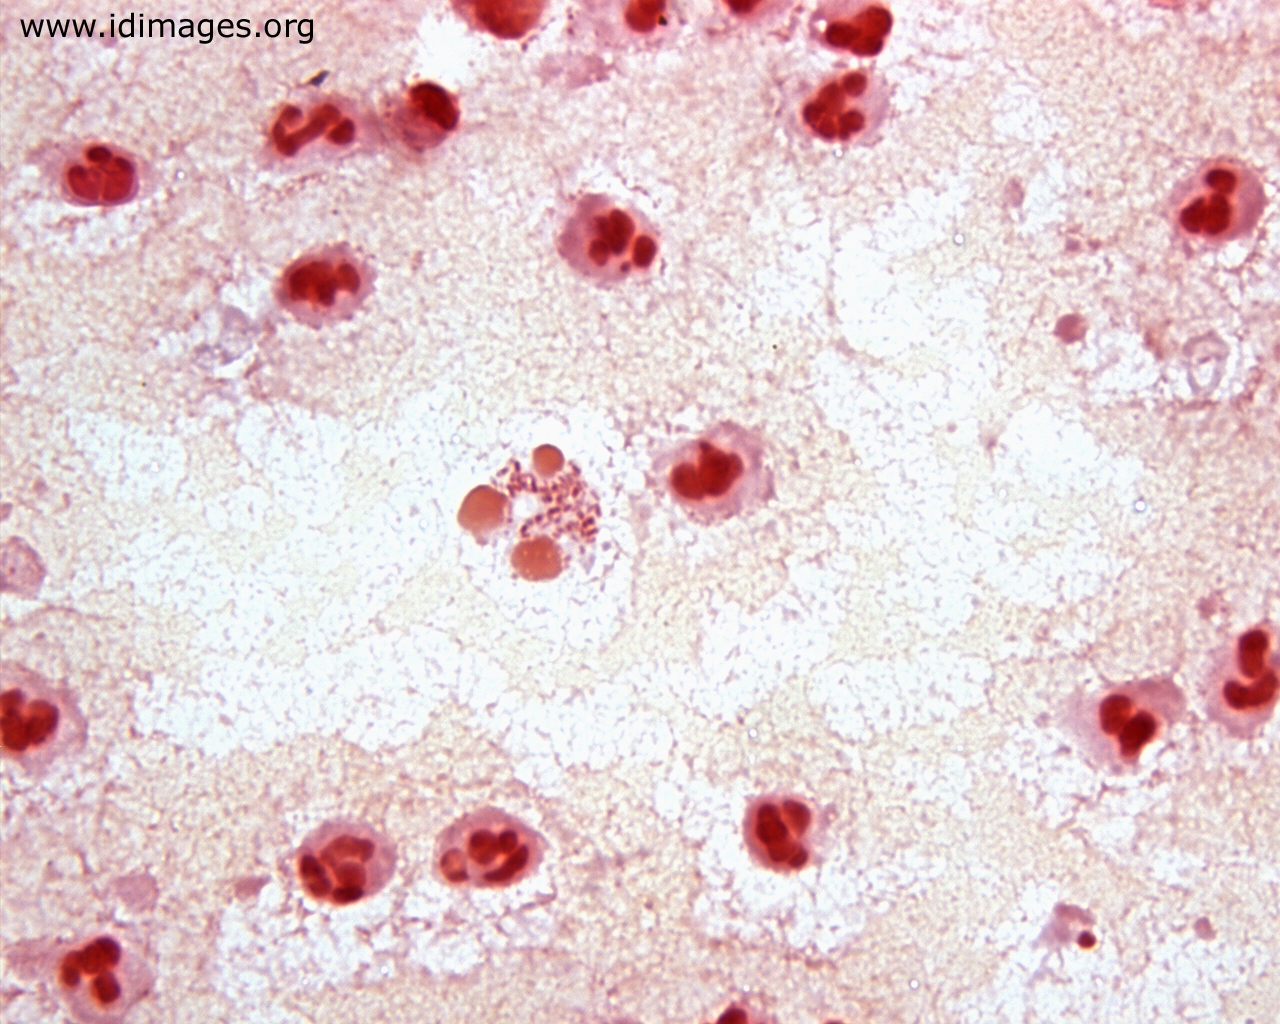

Saklı küre anlamına gelir.(Bkz; Crypto–coccus) Kapsüllü maya mantar cinsidir. yeşilliklerde epifit olarak büyürler. Cryptococcus gattii ökaliptüs ağacında büyür. Güvercinlerle kommensalizm ilişkisi vardır. Etkilediği organlar; Akciğer; genellikle farkedilmez, zayıf bağışıklıkta yayılırlar. Merkezi sinir sistemi;… Devamını oku